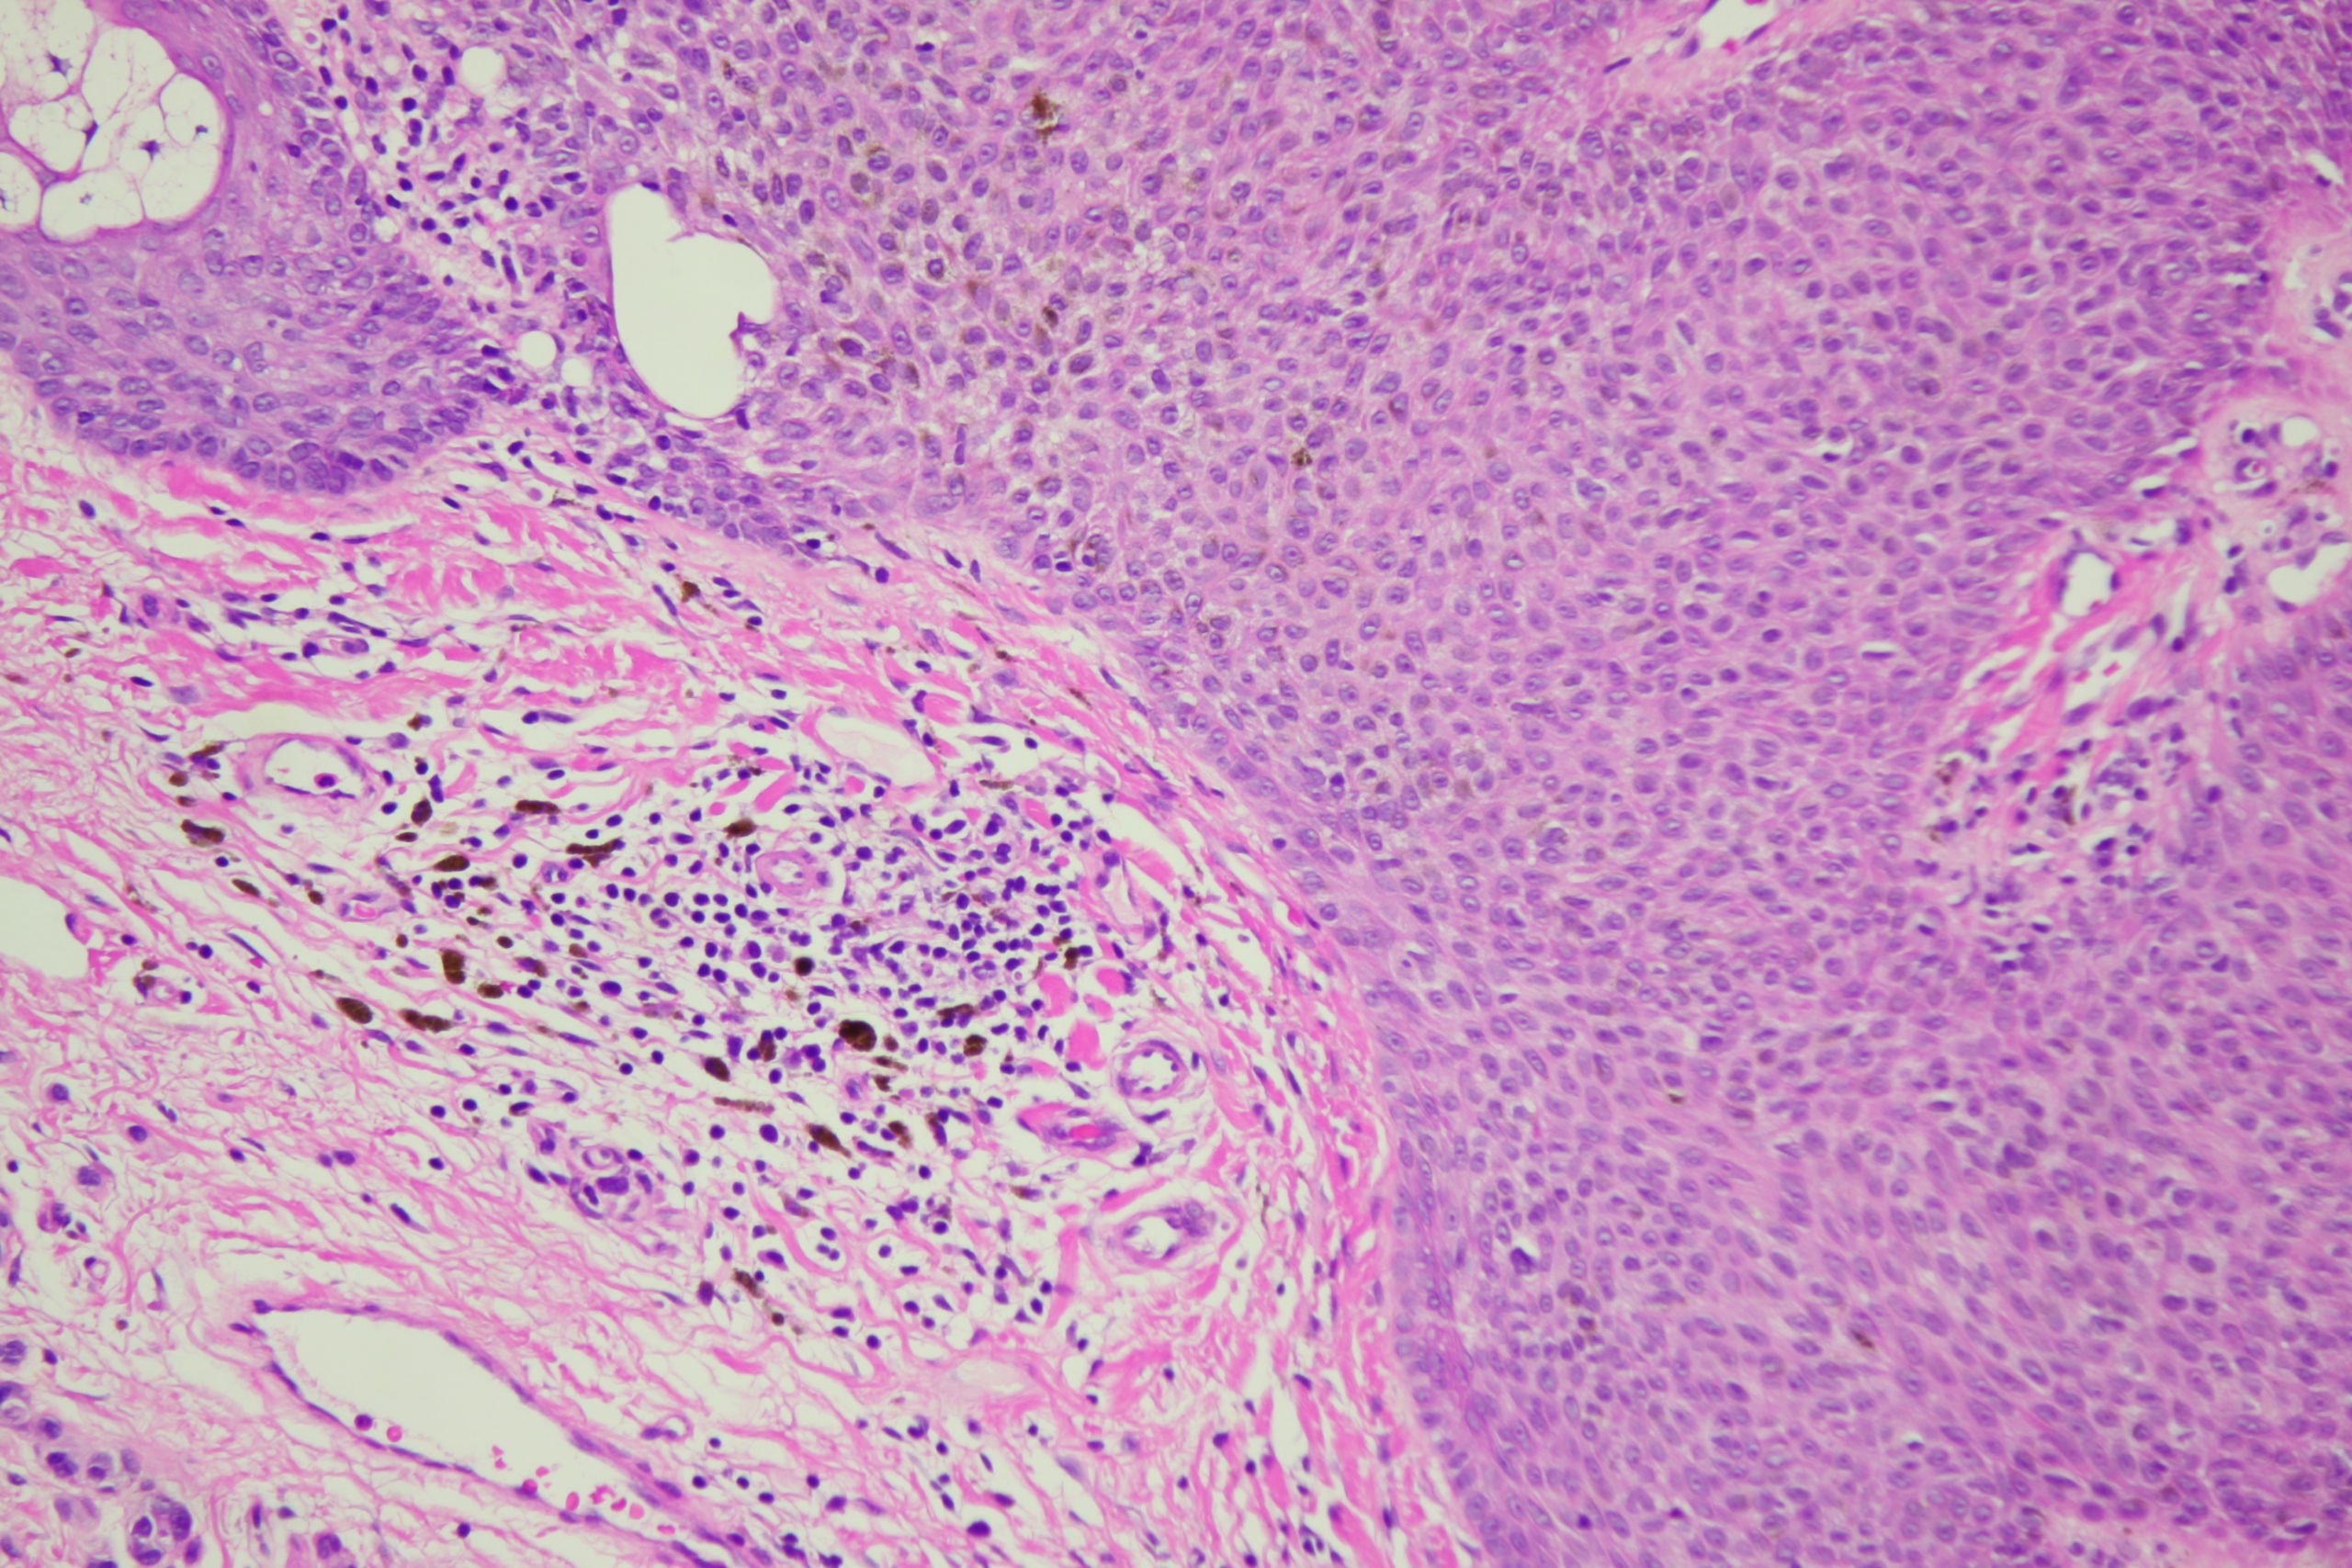

Image Number #3795 (Seborrhoeic keratosis irritated)

Diagnosis: Seborrhoeic keratosis irritated

Description: Dark blue blackish structureless areas surrounding paler center and white surface scales Broad coarse fatty brownish radial circumferential structures and black dots

A man in his 70s with this pigmented lesion on his upper back noted during a skin check.I look carefully at all dark seb k like lesions because lentigo maligna can easily involve a seb k. However I am always concerned about missing a seb k like melanoma. What do you think of this one? Note the pink colour surrounding it.